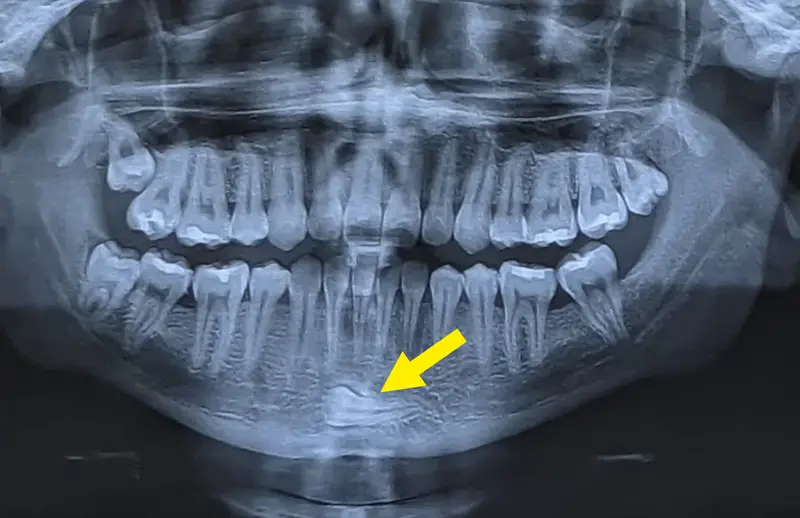

#8 Zub vo vnútri brady